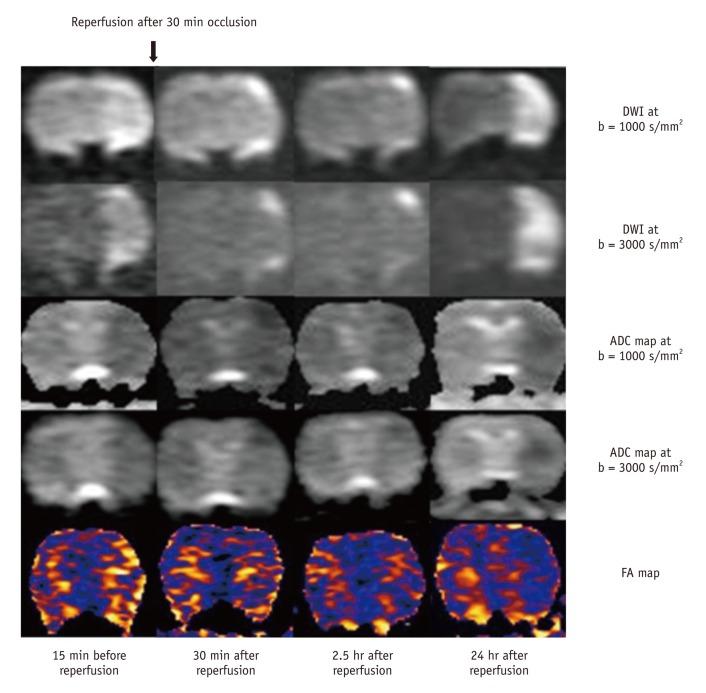

For permanent or 30-minute transient-ischemia induced 30 rats, DTI and DWIs at both high b (b = 3000 s/mm(2)) and standard b value (b = 1000 s/mm(2)) were obtained at the following conditions: at 15, 30, 45, 60 minutes after the occlusion of what for hyperacute permanent ischemia; at 1, 3, 5, 7, 9 hours after the occlusion for acute permanent ischemia; and at 15 minutes before reperfusion, 0.5, 2.5, and 24 hours after reperfusion for transient ischemia. The diffusion parameters and their ratios were obtained and compared between different b values, and among different time points and groups, respectively.

For both b values, the apparent diffusion coefficient (ADC) ratio decreased for first three hours, and then slightly increased until 9 hours after the occlusion during a gradual continuous increase of DWI signal intensity (SI) ratio, with excellent correlation between ADC ratios and DWI SI ratios. The DWI showed a higher contrast ratio, but the ADC map showed a lower contrast ratio for permanent ischemia at high b value than at standard b value. Fractional anisotropy (FA) increased for 1 hour, then gradually decreased until 9 hours after the occlusion in permanent ischemia and showed transient normalization and secondary decay along with change in ADC in transient ischemia.

This study presents characteristic initial elevation and secondary decay of FA, higher contrast ratio of DWI, and lower contrast ratio of ADC map at high b value, in addition to the time evolutions of diffusion parameters in early permanent and transient ischemia.